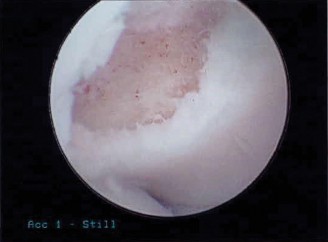

The correct answer is (A). The imaging demonstrates an axial CT scan with a large Hill–Sachs lesion. The lesion involves a large component of the humeral head (>40%) and as such is likely clinically significant. As the humerus is rotated externally the Hill–Sachs lesion is brought closer to the anterior rim of the glenoid and eventually engages the glenoid. Patients may perceive this as a painful click or locking episode. Lesions that involve 40% of the humeral head should be repaired to adequately address instability. The other answer choices all represent injuries that may be associated with a shoulder dislocation, although the large Hill–Sachs lesion is most responsible for his ongoing instability.

Hill–Sachs lesions are compression fractures of the posterosuperolateral

humeral head that occur when the head comes in contact with the glenoid during an acute anterior dislocation or after recurrent instability events. The relative incidence of these lesions is high, and it approaches 100% in patients with recurrent instability. It is important to understand that these lesions are bipolar—there is anterior glenoid damage in addition to the Hill–Sachs lesion; both of these must be addressed to optimize outcome. Lesions can be classified as engaging or nonengaging. Engaging lesions are oriented such that the long axis of the lesion is parallel to the anterior glenoid rim in the position of athletic function, i.e., abduction and external rotation. Engaging lesions tend to be more symptomatic, and instability may be associated with a sensation of catching or locking.

Physicians should obtain a complete set of x-rays. Special views include the modified Westpoint axillary (Fig. 2–43B) to evaluate for glenoid loss and the stryker notch view (Fig. 2–43A) to evaluate the Hill–Sachs lesion. This view brings the posterolateral defect into direct visualization. 3D CT imaging is also very useful for evaluating glenoid bone loss and estimating the size of the Hill–Sachs lesion.